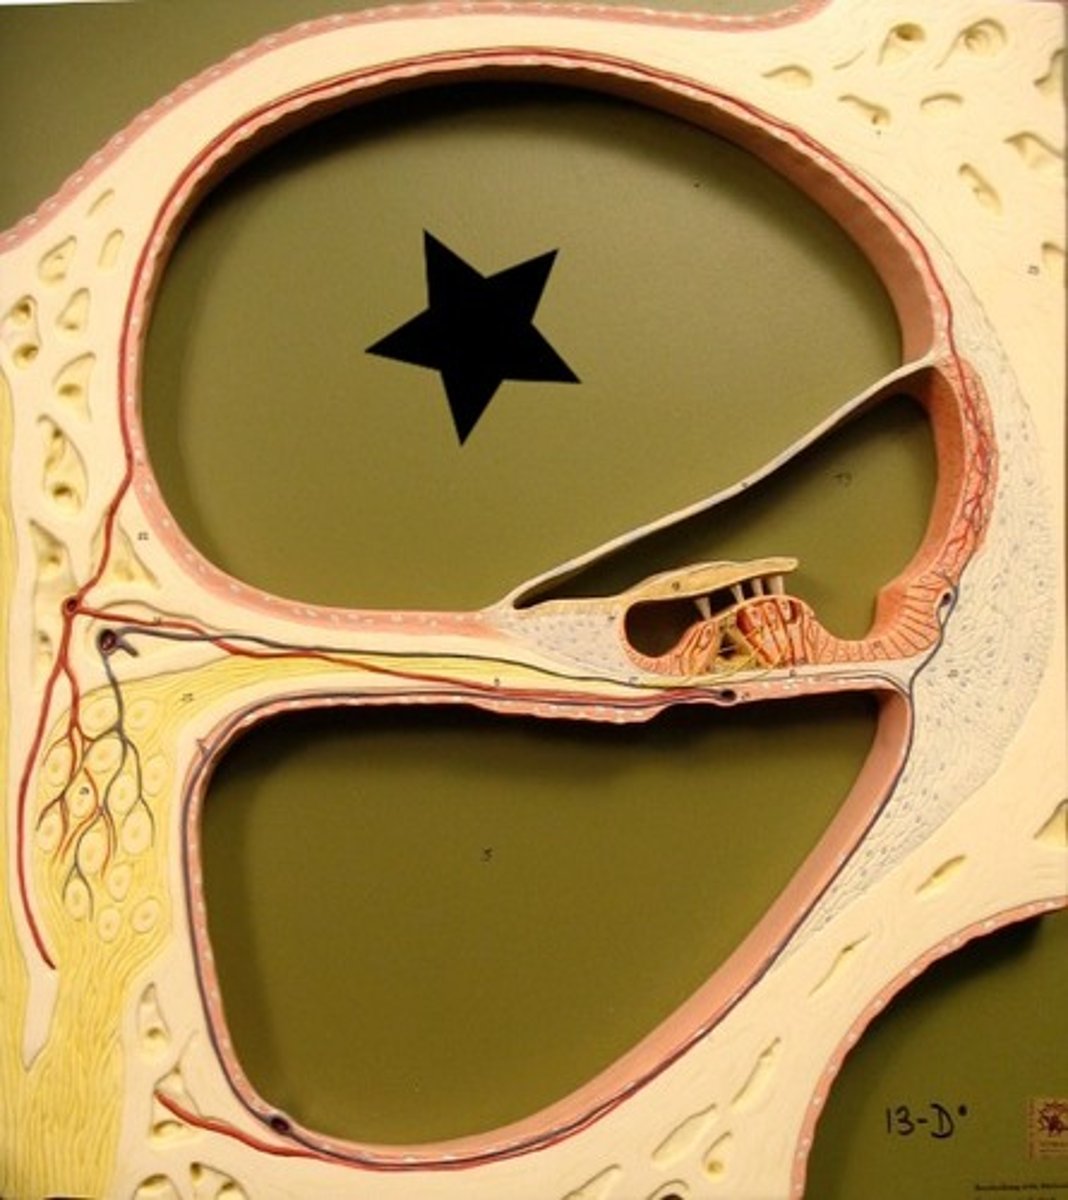

auditory tube

auricle (pinna)

cochlea

cochlear nerve

external auditory canal

incus

labyrinth (osseous + membranous)

malleus

oval window

round window

scala tympani

section of cochlea

scala vestibuli

section of cochlea

semicircular canals

spiral organ (of corti)

section of cochlea

stapes

temporal bone

tympanic membrane

vestibular nerve

vestibule

vestibulocochlear nerve